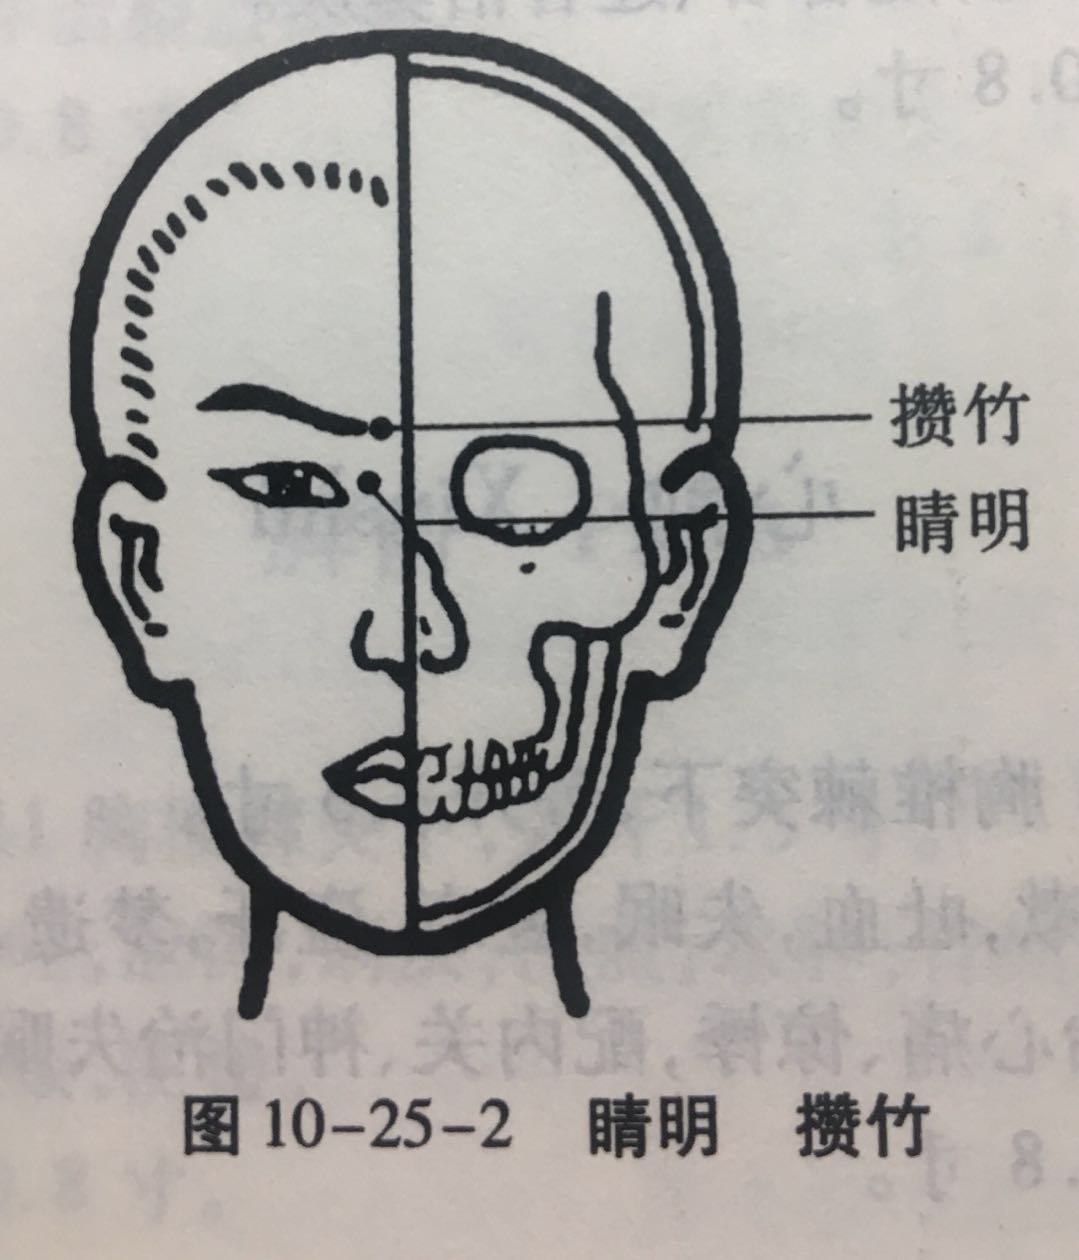

晴明

【定位】 在面部,目内眦角稍内上方凹陷处(图 10-25-2)。

【主治】 目赤肿痛,流泪,视物不明,目眩,近视,夜盲,色盲。

【配伍】 配球后、光明治视物不明。

【刺灸法】 嘱患者闭目,医者左手轻推轻推眼球向外侧固定,右手缓慢进针,紧靠眶缘直刺 0.5 ~ 1 寸。不捻转,不提插(或之轻微地捻转和提插)。出针后按压针孔片刻,以防出血。本穴禁灸。

【附注】 手足太阳、足阳明、阴跷、阳跷五脉交会穴。

攒竹

【定位】 在面部,当眉头凹陷处,约在目内眦直上(图 10-25-2)。

【主治】 头痛 ,口眼歪斜,目视不明,流泪,目赤肿痛,眼睑瞤(rún)动,眉棱骨痛,眼睑下垂。

【配伍】 配阳白治口眼歪斜、眼睑下垂。

【刺灸法】 平刺 0.5 ~ 0.8 寸。禁灸。